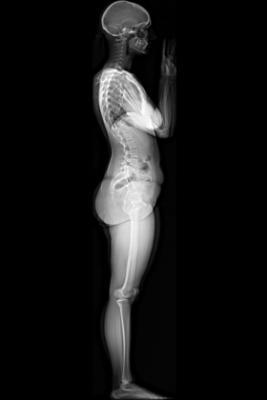

The EOS system provides full-body images of patients in a natural standing or seated position in both 2-D and 3-D. The system also delivers a radiation dose that has been measured to be nine times lower than that of computed radiography X-ray, and 20 times lower than basic CT scans. This is in accordance with the ALARA (As Low As Reasonably Achievable) principle of radiation reduction.